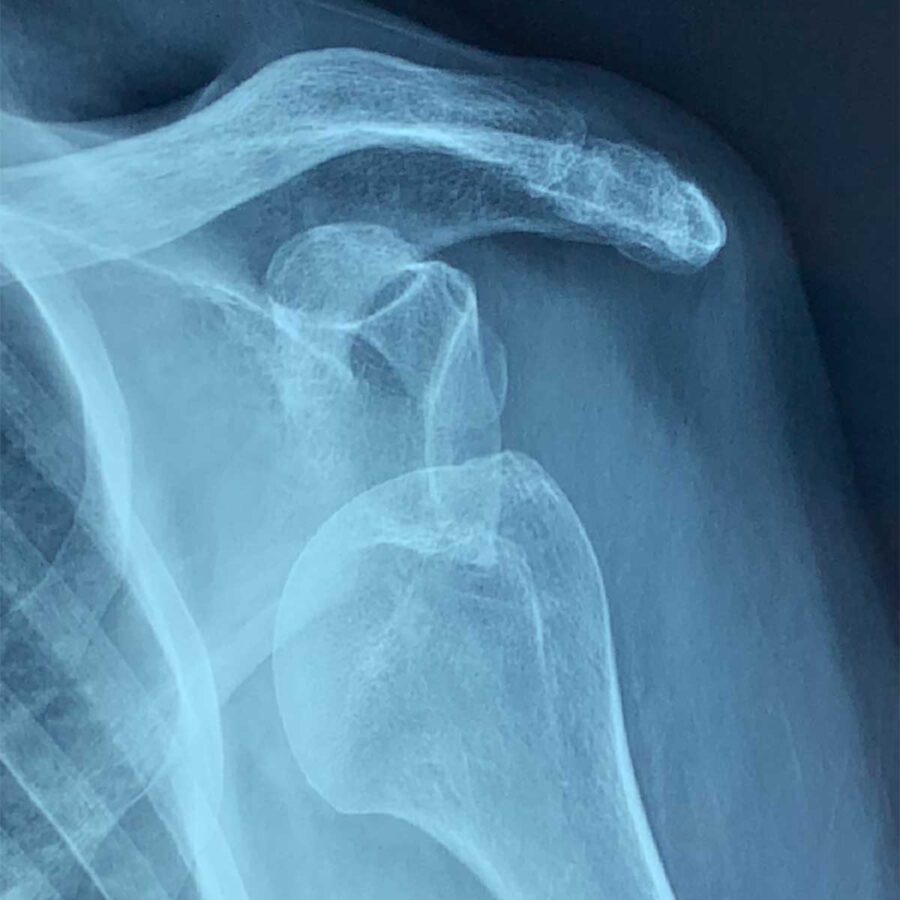

Si le patient continue à ressentir une appréhension ou une sensation d’instabilité, si le patient a un sport ou un métier l’exposant à la luxation, un avis chirurgical est demandé et une imagerie peut être prescrite (IRM, Scanner). Plus le patient est jeune et plus il sera envisagé de stabiliser l’épaule chirurgicalement.